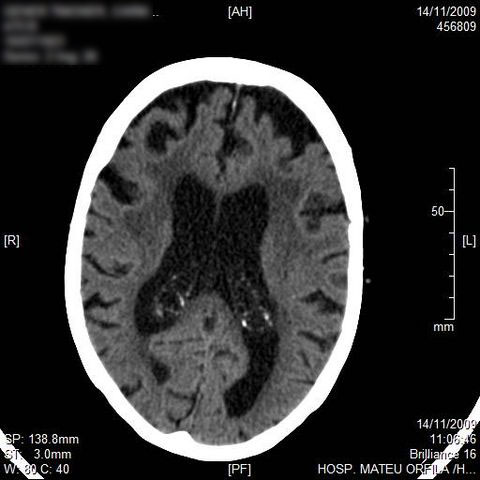

AVC amplio de territorio de A. cerebral media